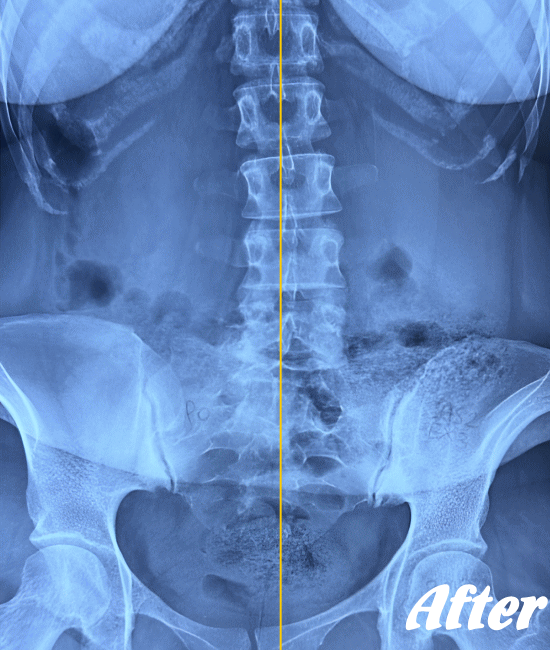

医療機関でも用いられているAKA療法を取り入れた施術により、身体に無理をかけず、ゆっくりと骨や関節の位置を解剖学的に正しい位置へ調整することで、痛みを取り除いていきます。慢性化した痛みも改善します。

多くの場合、骨盤の仙腸関節、腰の骨(腰椎)、そして足の付け根の股関節を調整すれば、痛みはなくなり、健康な状態に回復します。

ぎっくり腰程度であれば、初回の施術で腰が伸ばせる程度までには回復し、2回目の施術で残った痛みを取り除き、3回目で最後の違和感を解消します。